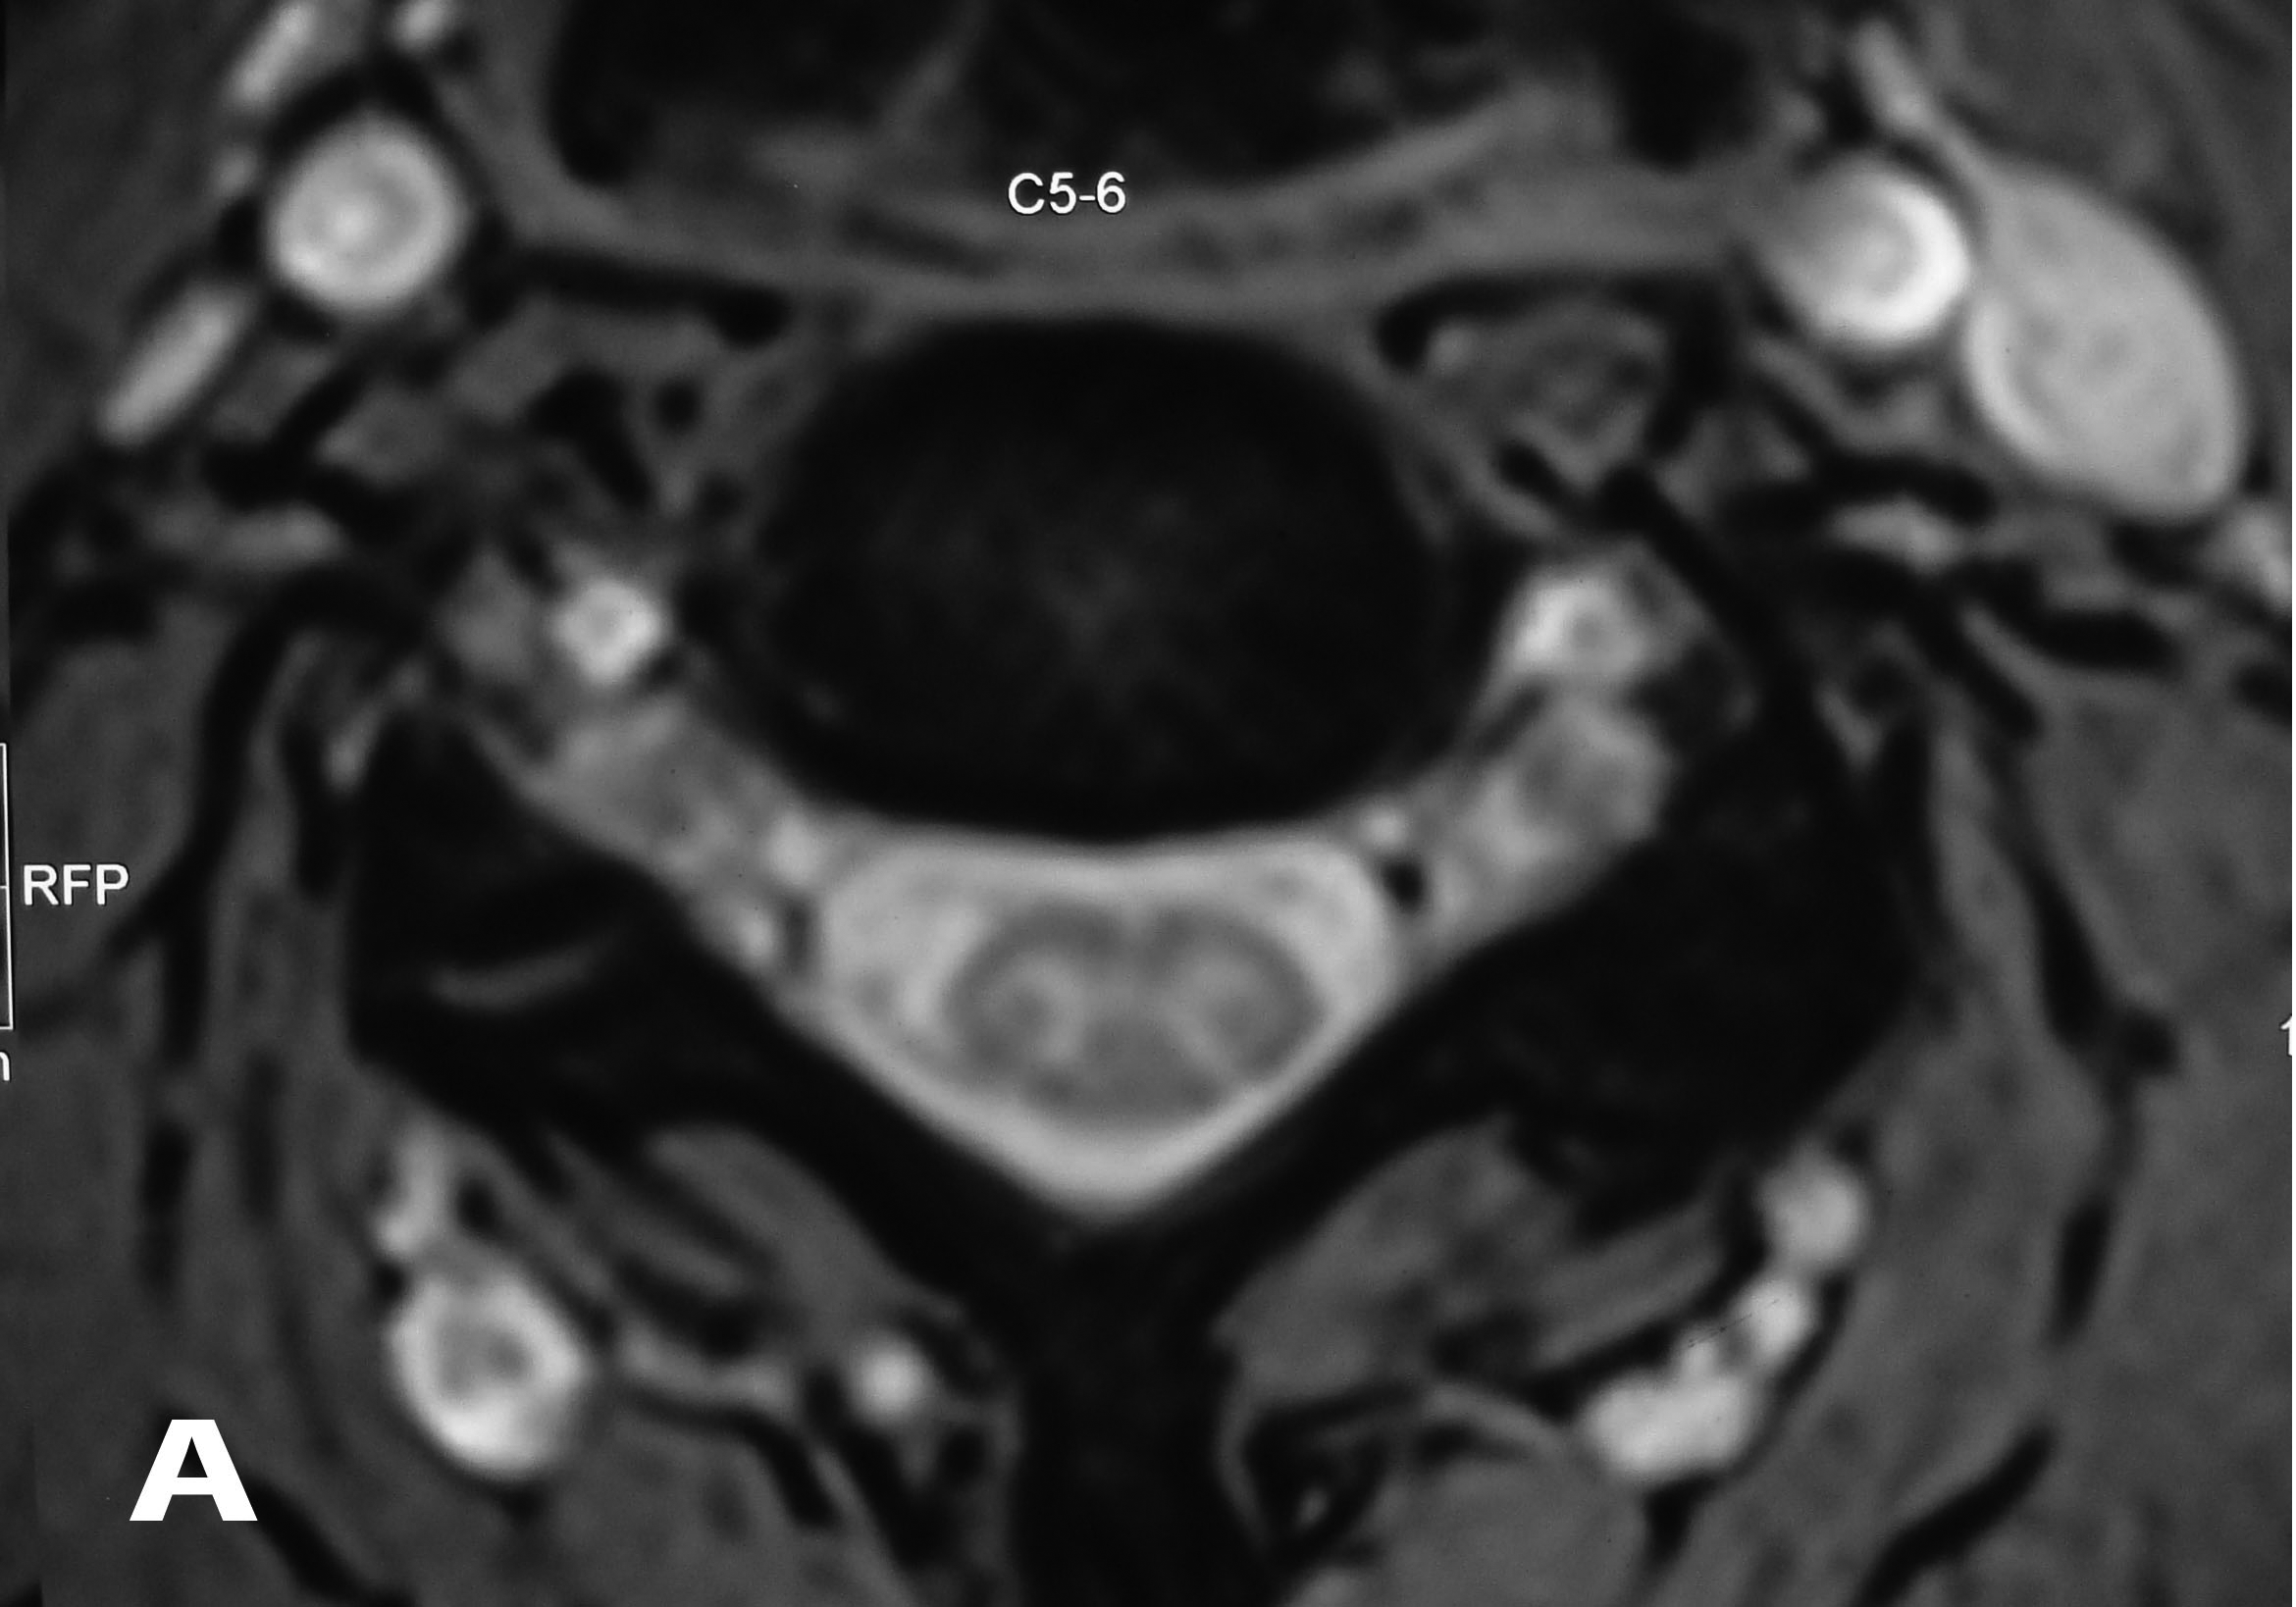

Plain radiographs showed no abnormalities. MRI of the cervical spine was done. Sagittal T2W images showed hyperintense lesion at both C5-C6 neural foramen (Figure 1 & 2). Axial T2W images showed bilateral cervical perineural cyst at C5-C6 neural foraminae (Figure 3A & 3B). Post-contrast study showed no abnormal enhancement along the cysts. EMG-NC studies showed evidence of C5C6 chronic motor axon degeneration at root level. Left deltoid and biceps showed high amplitude large duration motor unit potentials during voluntary activity.

Figure 1 Sagittal T2W image of the cervical spine showing hyperintense lesion at C5-C6 neural foramen corresponding to the right perineural cyst.

Figure 3A & B Axial T2W images of the cervical spine demonstrating bilateral cervical perineural cyst at the C5-C6 level.